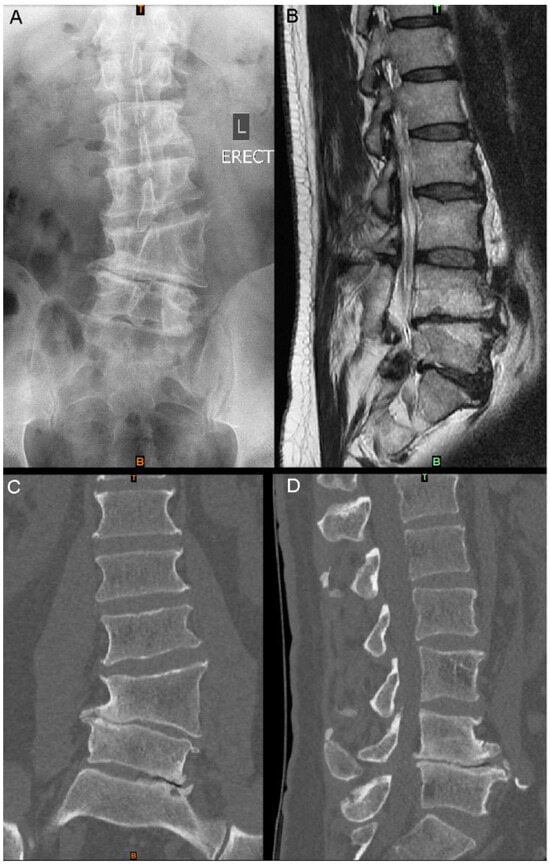

Figure 1.

Imaging at presentation: (A) standing AP X-ray; (B) sagittal slice of T2 MRI of the lumbar spine; (C) lumbar spine CT coronal slice; (D) lumbar spine CT sagittal slice at a similar position to (B).

A 53-year-old man presented with a 12-month history of severe, progressive back and bilateral leg pain (visual analogue scale (VAS) pain score of 8/10). No deficits in sensory or motor deficits were present on examination; however, the patient reported difficulty in performing occupational tasks. The patient reported a background of chronic lower-back pain since childhood, secondary to an L4 lateral hemivertebra diagnosed in adolescence. Conservative management had successfully provided symptomatic relief until the recent onset of leg pain. CT imaging demonstrated the long-standing L4 hemivertebra and mild congenital scoliosis, as well as associated degenerative changes at the L4/5 and L5/S1 levels, including a loss of disc and neuroforaminal heights, and extensive osteophytosis (Figure 1 and Figure 2).